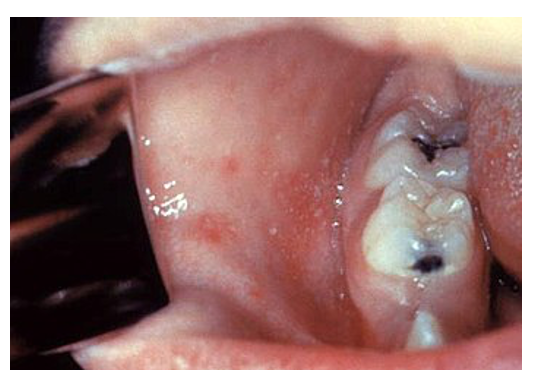

– Koplik spots –> white spots (“grains of salt”) on cheek which appear before rash

– Rash –> This starts on the face and spreads to rest of the body (day 3-5)

– It is a maculopapular rash that becomes blotchy and confluent